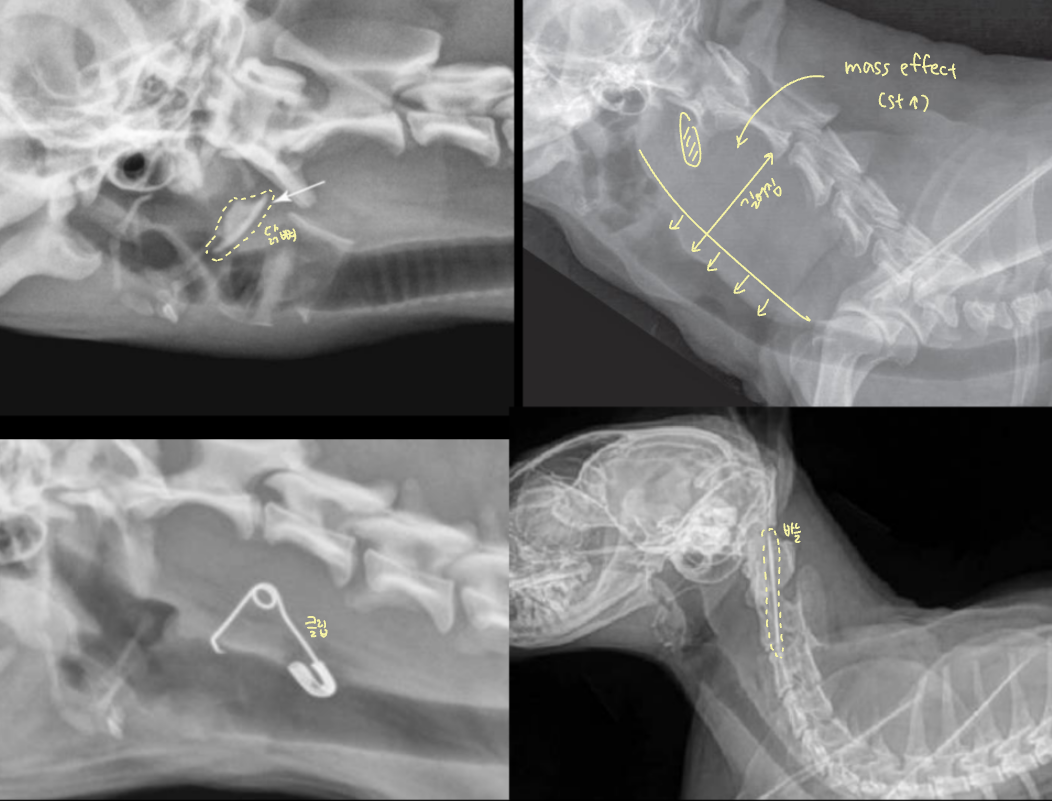

Brachycephalic syndrome

단두종

- English bulldog, Pug, Pekingese, French Bulldog, Bonston Terrier..

==Complex==

- stenotic nares (비공협착)

- soft palate edema & elongation (연구개노장)

- laryngeal edema, saccules, collapase, paralysis

- (dynamic) pharyngeal collapse

GI complication

- Hiatal hernia

- gastroesophageal reflux (역류성 식도염)

Pharyngeal collapse : 호기 때 좁아짐

- 증상은 흡기에서 더 심함 (흡기성 호흡곤란)